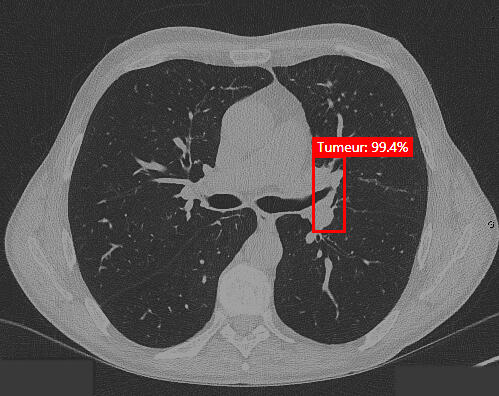

Hekia continues to test its artificial intelligence solutions to detect other diseases such as lung, skin and breast cancers. These projects are in their early stages and will require new partnerships, so if you're interested or have a research project to propose, get in touch!